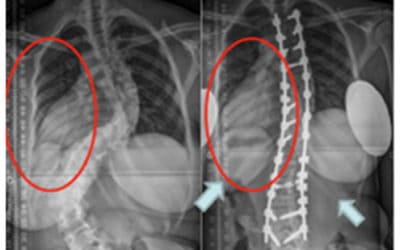

Rehabilitasi Skoliosis Pasca Operasi

Rehabilitasi skoliosis pasca operasi adalah proses pemulihan yang penting setelah seseorang menjalani operasi untuk mengoreksi kelengkungan abnormal tulang belakangnya. Tujuannya adalah untuk membantu pasien pulih secara optimal setelah operasi, memperkuat otot-otot...